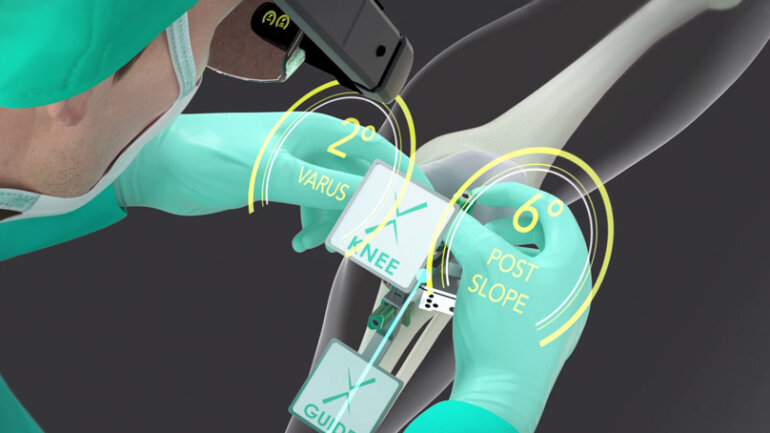

Αρθροπλαστική γόνατος: Ποια αθλήματα επιτρέπονται και μετά από πόσο χρονικό διάστημα είναι ασφαλής η επιστροφή;

Η ολική αρθροπλαστική γόνατος αποτελεί τη μοναδική οριστική θεραπεία της οστεοαρθρίτιδας τελικού σταδίου.